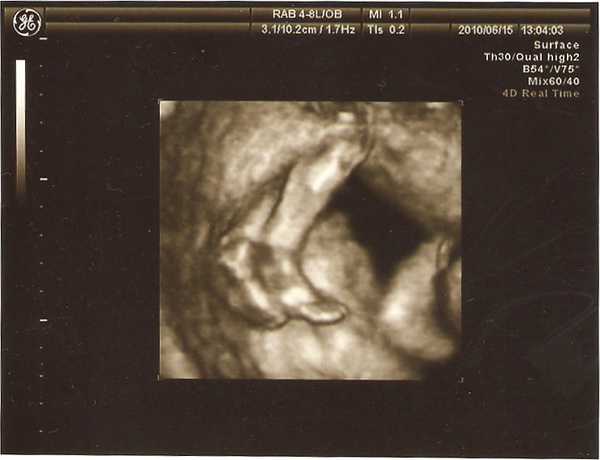

十指健全

這是他的腳,睡到蹺腳~